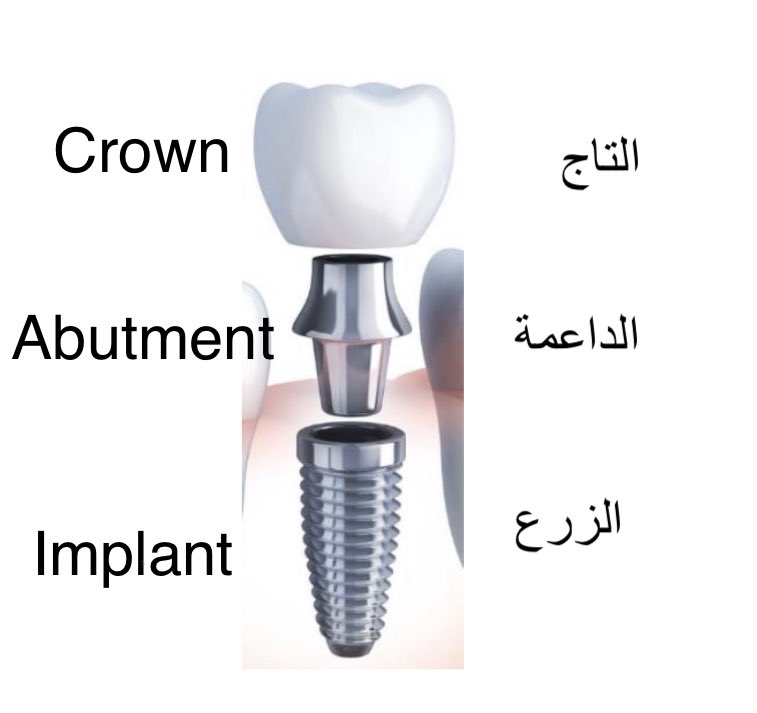

🦷 أجزاء الزرعة :

هناك بشكل عام 3 أجزاء و هم :

التاج ——> Crown

الداعمة ——> Abutment

الزرع ———> Implant

هناك بشكل عام 3 أجزاء و هم :

التاج ——> Crown

الداعمة ——> Abutment

الزرع ———> Implant